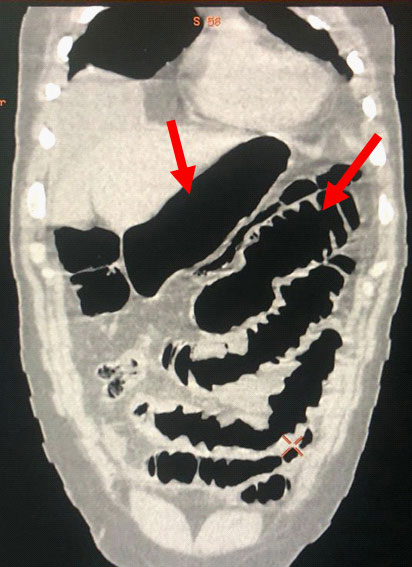

A 56-year-old male patient, who was previously healthy, was admitted to the emergency room of Hospital da Cidade – Salvador – Bahia – Brazil due to diffuse abdominal pain that started 24 hours before admission, with progressive worsening and intensity 9, on a 0-10 scale. During physical examination he was tachycardic (HR > 90 bpm), tachypneic (RR > 20), normotensive, in antalgic position and had distended abdomen with diffuse pain on decompression and poor response to opioid analgesics. He did not have systemic inflammatory response syndrome (SIRS) and laboratory tests, including white blood cell count and pancreatic enzymes were normal. The radiological routine for acute abdomen was not clarifying and thus, contrasted Computed Tomography (CT) of the abdomen was performed, showing: Free fluid in the abdominal cavity and important jejunal and gastric distension (Figures 1 & 2). The distension of the small intestine made it impossible to access the abdominal cavity by laparoscopy. Exploratory Laparotomy (EL) was performed which showed large amounts of enteric fluid in all abdominal quadrants, significant edema of the small bowel loops and multiple jejunal diverticula (Figure 3). One of them was perforated and located 30 cm from the Treitz angle (Figure 4), which was defined by segmental enterectomy of approximately 20cm (figure 5). Primary lateral-lateral anastomosis was performed using a linear stapler for intestinal reconstruction and cleaning of the abdominal cavity until clear return of the aspirate. There was a postoperative period in the intensive care unit (ICU) for 3 days, due SIRS and necessity of the clinical and laboratorial surveillance. During that time, nutritional therapy with Total Parenteral Nutrition (TPN) was started early. After improvement in abdominal distension and removal of the nasogastric tube on the 7th day after surgery (POD), an oral liquid diet without residues was introduced. There were no postoperative complications or need for surgical re-approach. Finally, the patient was discharged on the 11th POD with a mild oral diet, without complaints and with a normal bowel rhythm. There was no readmission.

Figure 2:Abdominal tomography sagittal section: Massive distension of intestinal loops (Red arrows).